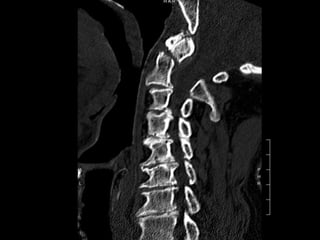

55 year old woman with central axial neck pain with

no radiculopathy; no signs or symptoms of myelopathy.

No history of trauma PMH: hypothyroidism in general

healthy

55 year oldwoman with central axial neck pain with no radiculopathy; no signs or symptoms of myelopathy. No history of trauma PMH: hypothyroidism in general healthy